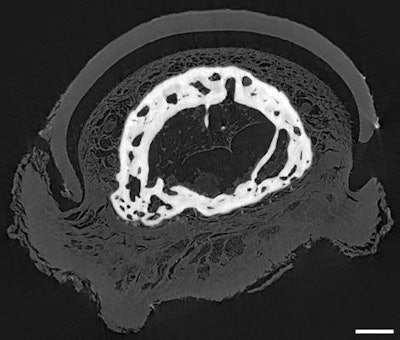

Evaluating the technique in a laboratory setting, Romell and colleagues performed phase-contrast CT scans on an Egyptian mummy dated to around 400 B.C. They first acquired nine scans of distinct regions of the mummy's hand and then combined these scans into a single dataset using image reconstruction software (Octopus Reconstruction, XRE).

To get an even more detailed look, the group acquired a phase-contrast CT scan of just the tip of the mummy's middle finger. The reduced surface area enabled them to maximize phase contrast by using smaller equipment that provided greater magnification, as well as by increasing the exposure time per scan.

On the volume-rendered images of the entire mummy hand, the researchers were able to visualize the hand bones with comparable resolution to that of micro-CT. They estimated that the mummy was a boy between 13 and 17 years old at the time of his death based on his bone development. Phase-contrast CT scans of the hand also helped them to identify linen, skin, tendons, and ligaments, as well as larger nerves and arteries such as the ulnar nerve and artery.

The phase-contrast CT scans of the isolated fingertip revealed additional features not observed on the scans of the hand, including microvessels and tiny nerves in the nail bed, fat cells (i.e., adipocytes), and traces of bone marrow. Romell and colleagues found that this anatomy had excellent correspondence with the detailed anatomy presented in contemporary medical textbooks.